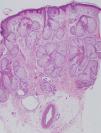

Se realizó biopsia cutánea frontal derecha que objetivó importante hiperplasia sebácea, sin otras alteraciones (fig. 2). Se solicitó analítica rutinaria añadiendo C1q inhibidor, hormonas tiroideas, autoinmunidad, marcadores tumorales, ácido vanilmandélico, catecolaminas y 5 hidroxi-indolacético (5-HIA) en orina de 24h. En los resultados destacó una discreta anemia, velocidad de sedimentación globular 70 y 5-HIA en orina muy elevado (339mg/24h con un control de 1–8,2mg/24h). En la radiografía de tórax se apreció una imagen residual parahiliar derecha, que permanecía estable respecto a controles previos. En la tomografía axial computarizada toraco-abdominal se puso de manifiesto la presencia de metástasis hepáticas no visibles en la que se realizó 8 meses antes (fig. 3). En el Servicio de Otorrinolaringología se diagnosticó una hipoacusia de conducción por edema de ambos conductos auditivos externos. En Oftalmología se objetivó una disminución del campo visual por engrosamiento palpebral. La serie ósea realizada fue normal.